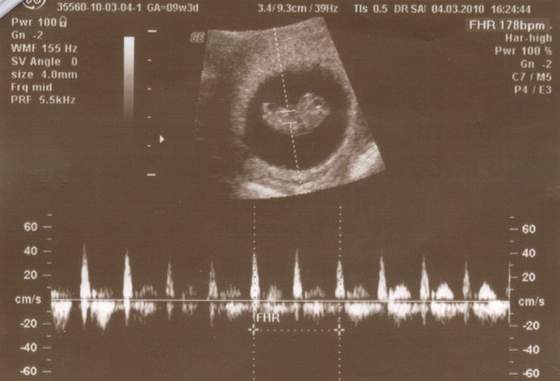

Oj widze ze dla moriam i joanna0984 dzieciaczki sie pleckami odwrucily ;-) Slodziaki!